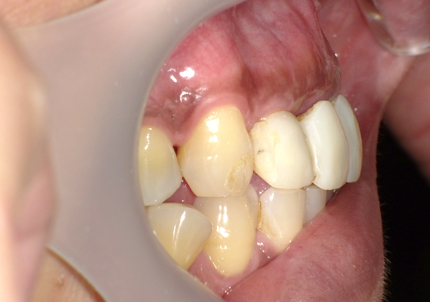

1.初診時口腔内写真(2014年6月)

2.治療終了(2016年6月)

・上顎補綴物再製

・右下2本インプラント

・左下ジルコニアクラウンブリッジ